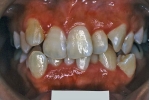

日本矯正歯科学会専門医課題症例(第4症例)

カテゴリー:ClassⅡ division 2 malocclusion (Overbite 5mm以上; 抜歯症例)

しかし、出題基準にも書いてあるように、このケースは欧米の白人によく見られるケースで、東洋人にはきわめて稀である。そこで類似ケースとして過蓋咬合(かがいこうごう)のケースを代替えとして認めるという配慮をしている。過蓋咬合とは非常に強く深く咬んでいる状態を言う。Overbiteとは前歯の垂直的な重なり具合を示す数値で、5mm以上だと上の前歯が下の前歯をほとんど覆い尽くしている感じになるので、前から見ると下の前歯はほとんど見えない状態になる。こういう状態が典型的な過蓋咬合である。典型的なclassⅡ,division 2のケースは過蓋咬合を合併している。

| 治療後3年経過時